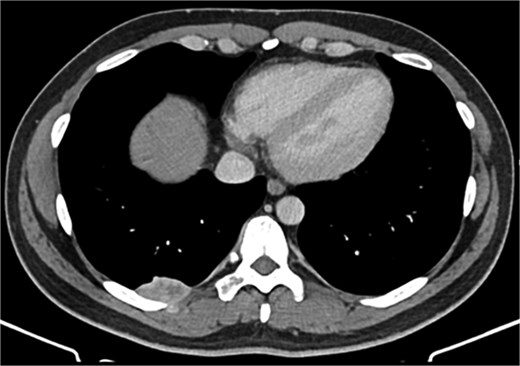

A 42-year-old male patient presented with intermittent pain under the right scapula for one year. The pain occurred both day and night, radiated to the right side of the abdomen, and improved with exercise. No skin lesions were observed. A thoracic spine magnetic resonance imaging scan showed a well-defined subpleural lesion on the right side along the ninth intercostal space posteriorly, which was hyperintense on T1-weighted imaging and isointense on T2-weighted imaging, with contrast enhancement features. The lesion size was 38 × 18 mm and extends into the back muscles with an additional nodule of 6 × 9 mm (Fig. 1). A contrast-enhanced computed tomography (CT) scan of the chest was performed to obtain a comprehensive chest view, revealing the same lesion without any other pathological findings (Fig. 2).